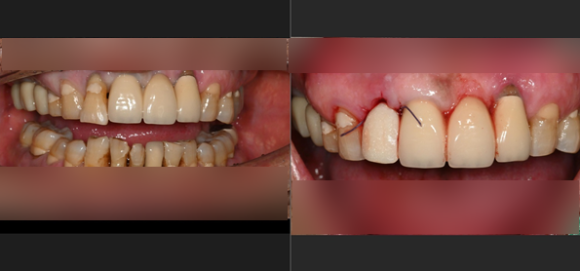

뼈가 부족할 때는 골유도재생술(GBR)이라는 고난도 기법을 사용합니다.

단순히 인공뼈를 채워 넣는 것이 아니라, 뼈가 잘 차오를 수 있도록 특수 차폐막을 덮어주는 정교한 과정이 필요합니다.

• 인공뼈 이식: 환자 본인의 뼈(자가골)나 검증된 인공뼈를 이식합니다.

• 차폐막 활용: 잇몸 세포가 뼈가 자랄 공간을 방해하지 못하도록 막아주어, 단단한 뼈가 형성될 시간을 벌어줍니다.